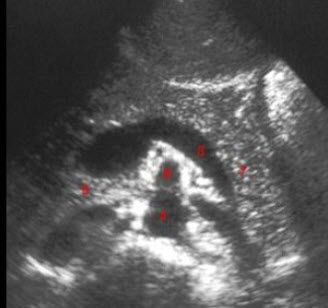

29、单项选择题

图示7所指部位()

A.脾静脉

B.胃

C.胰尾

D.第二肝门

E.左肾上腺